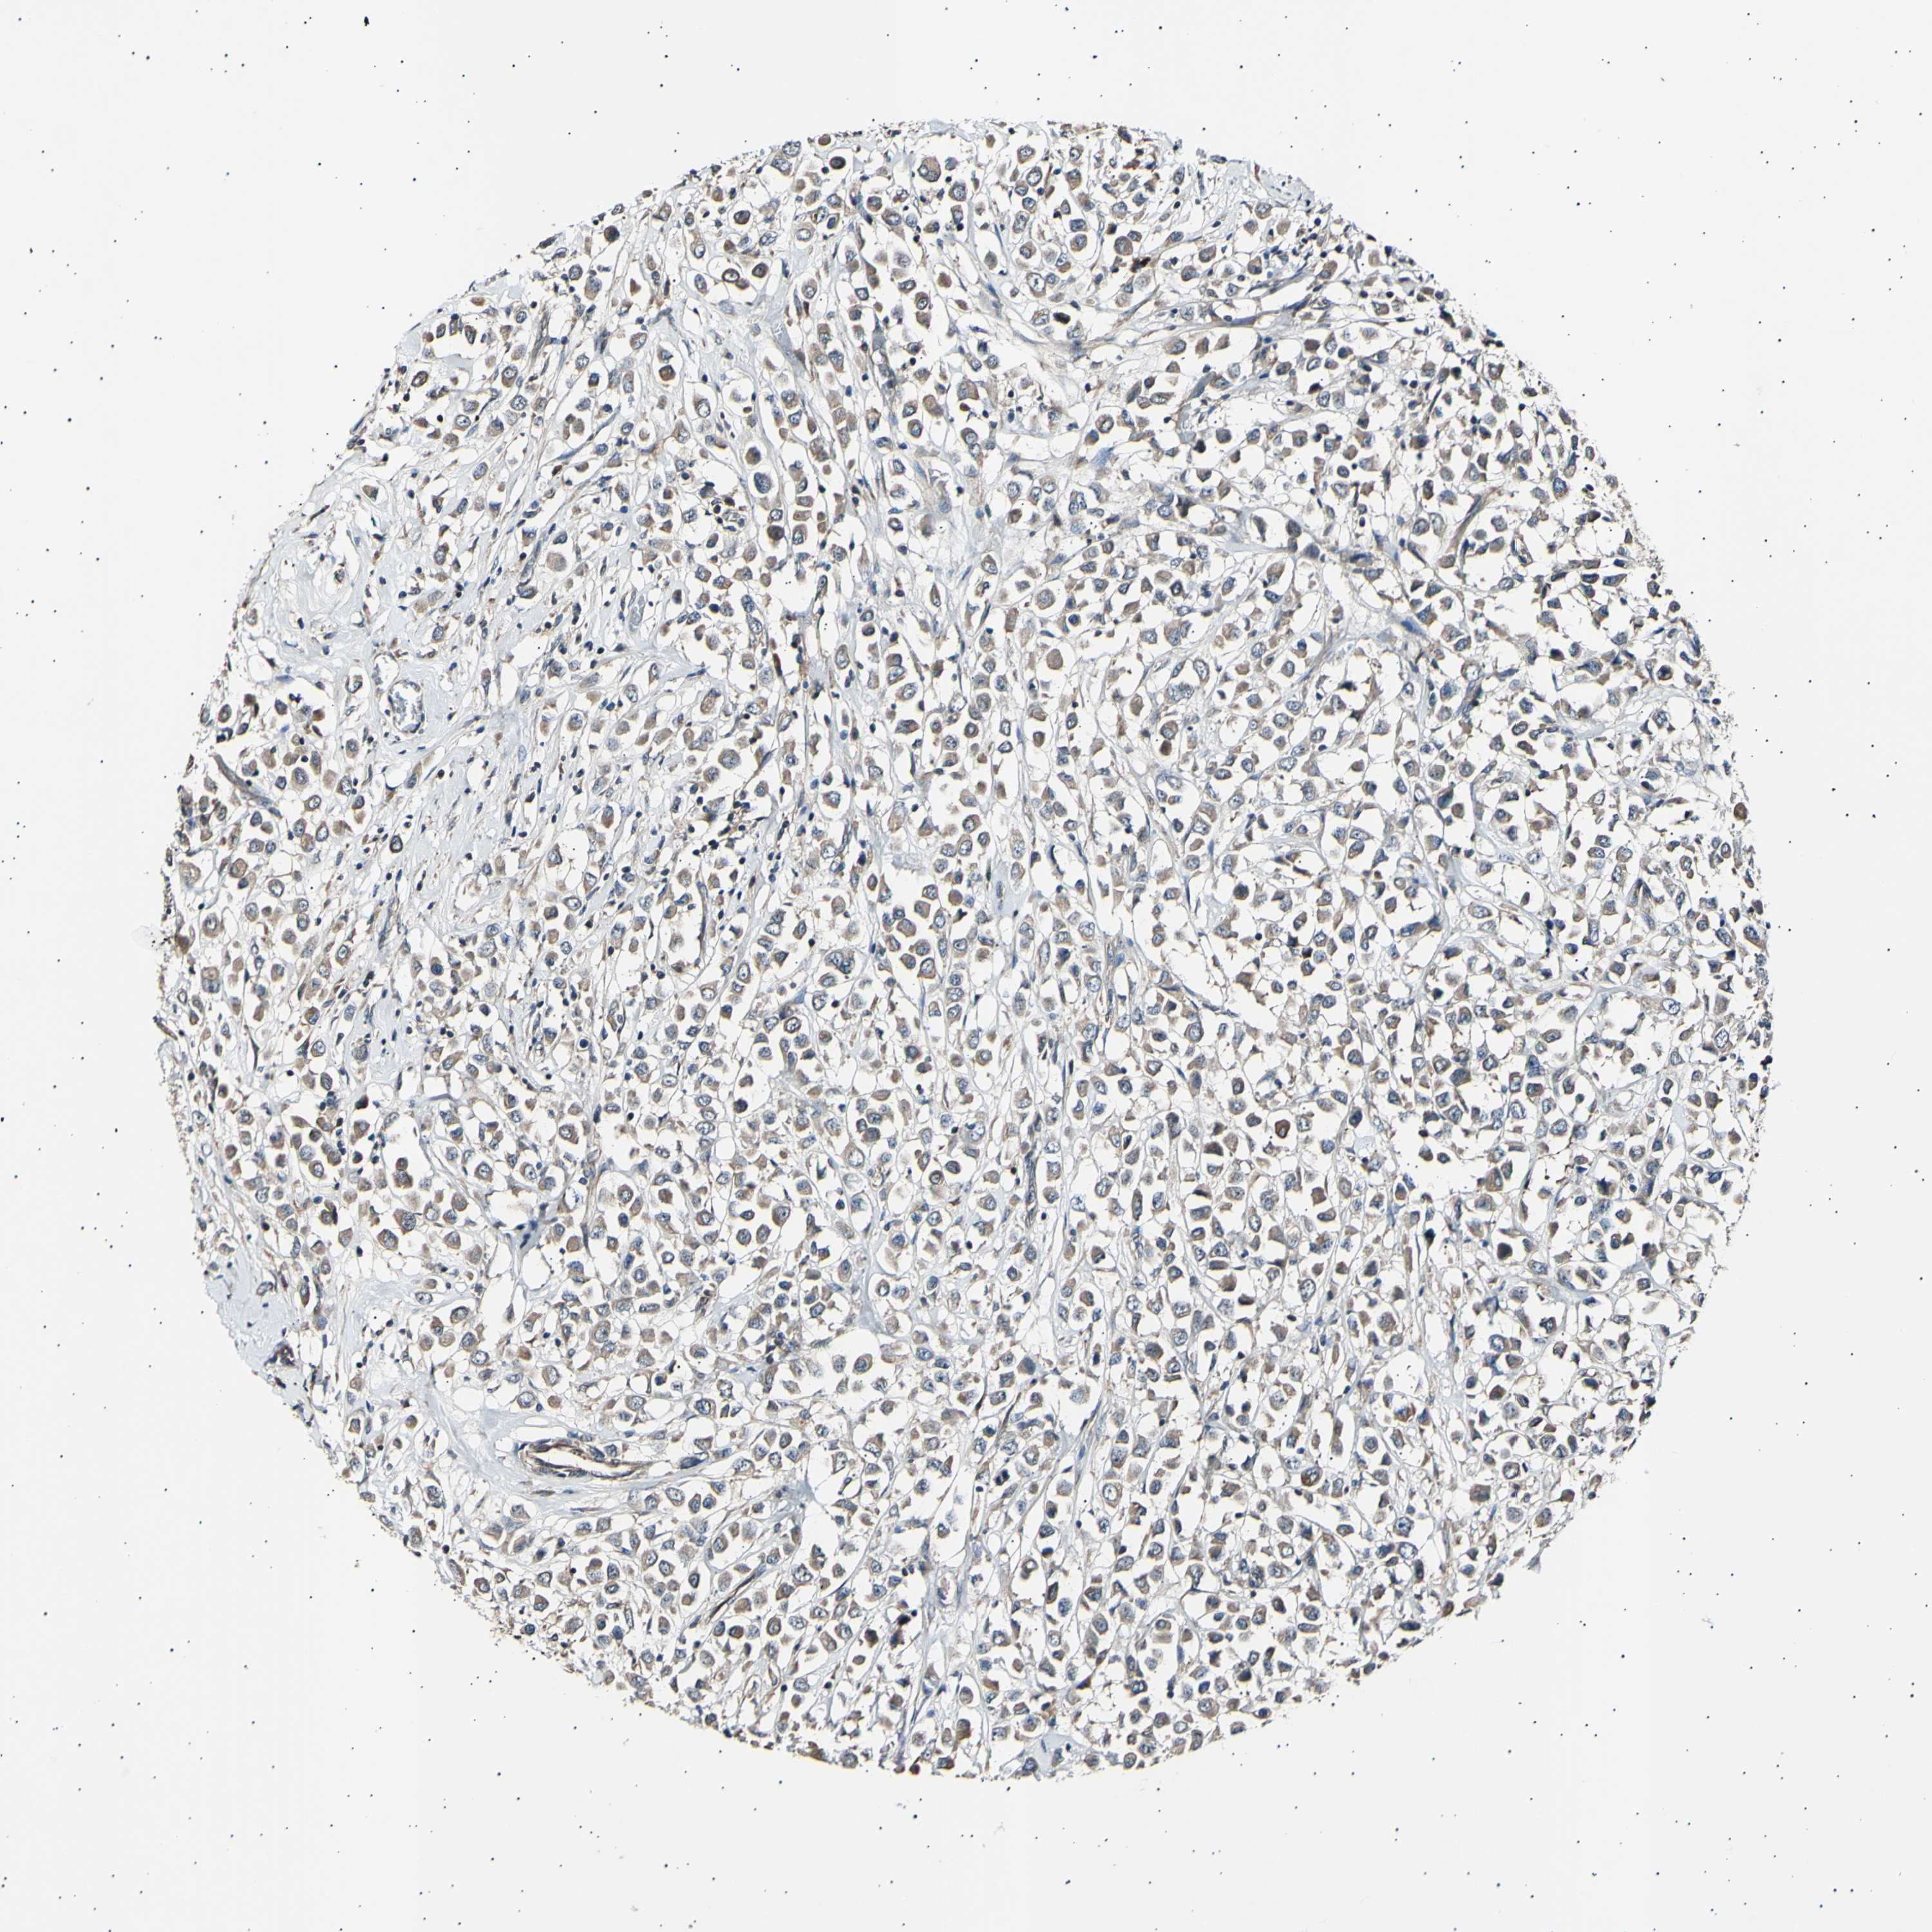

BRCA TCGA BRCA VALIDATION PROTEIN EXPRESSION